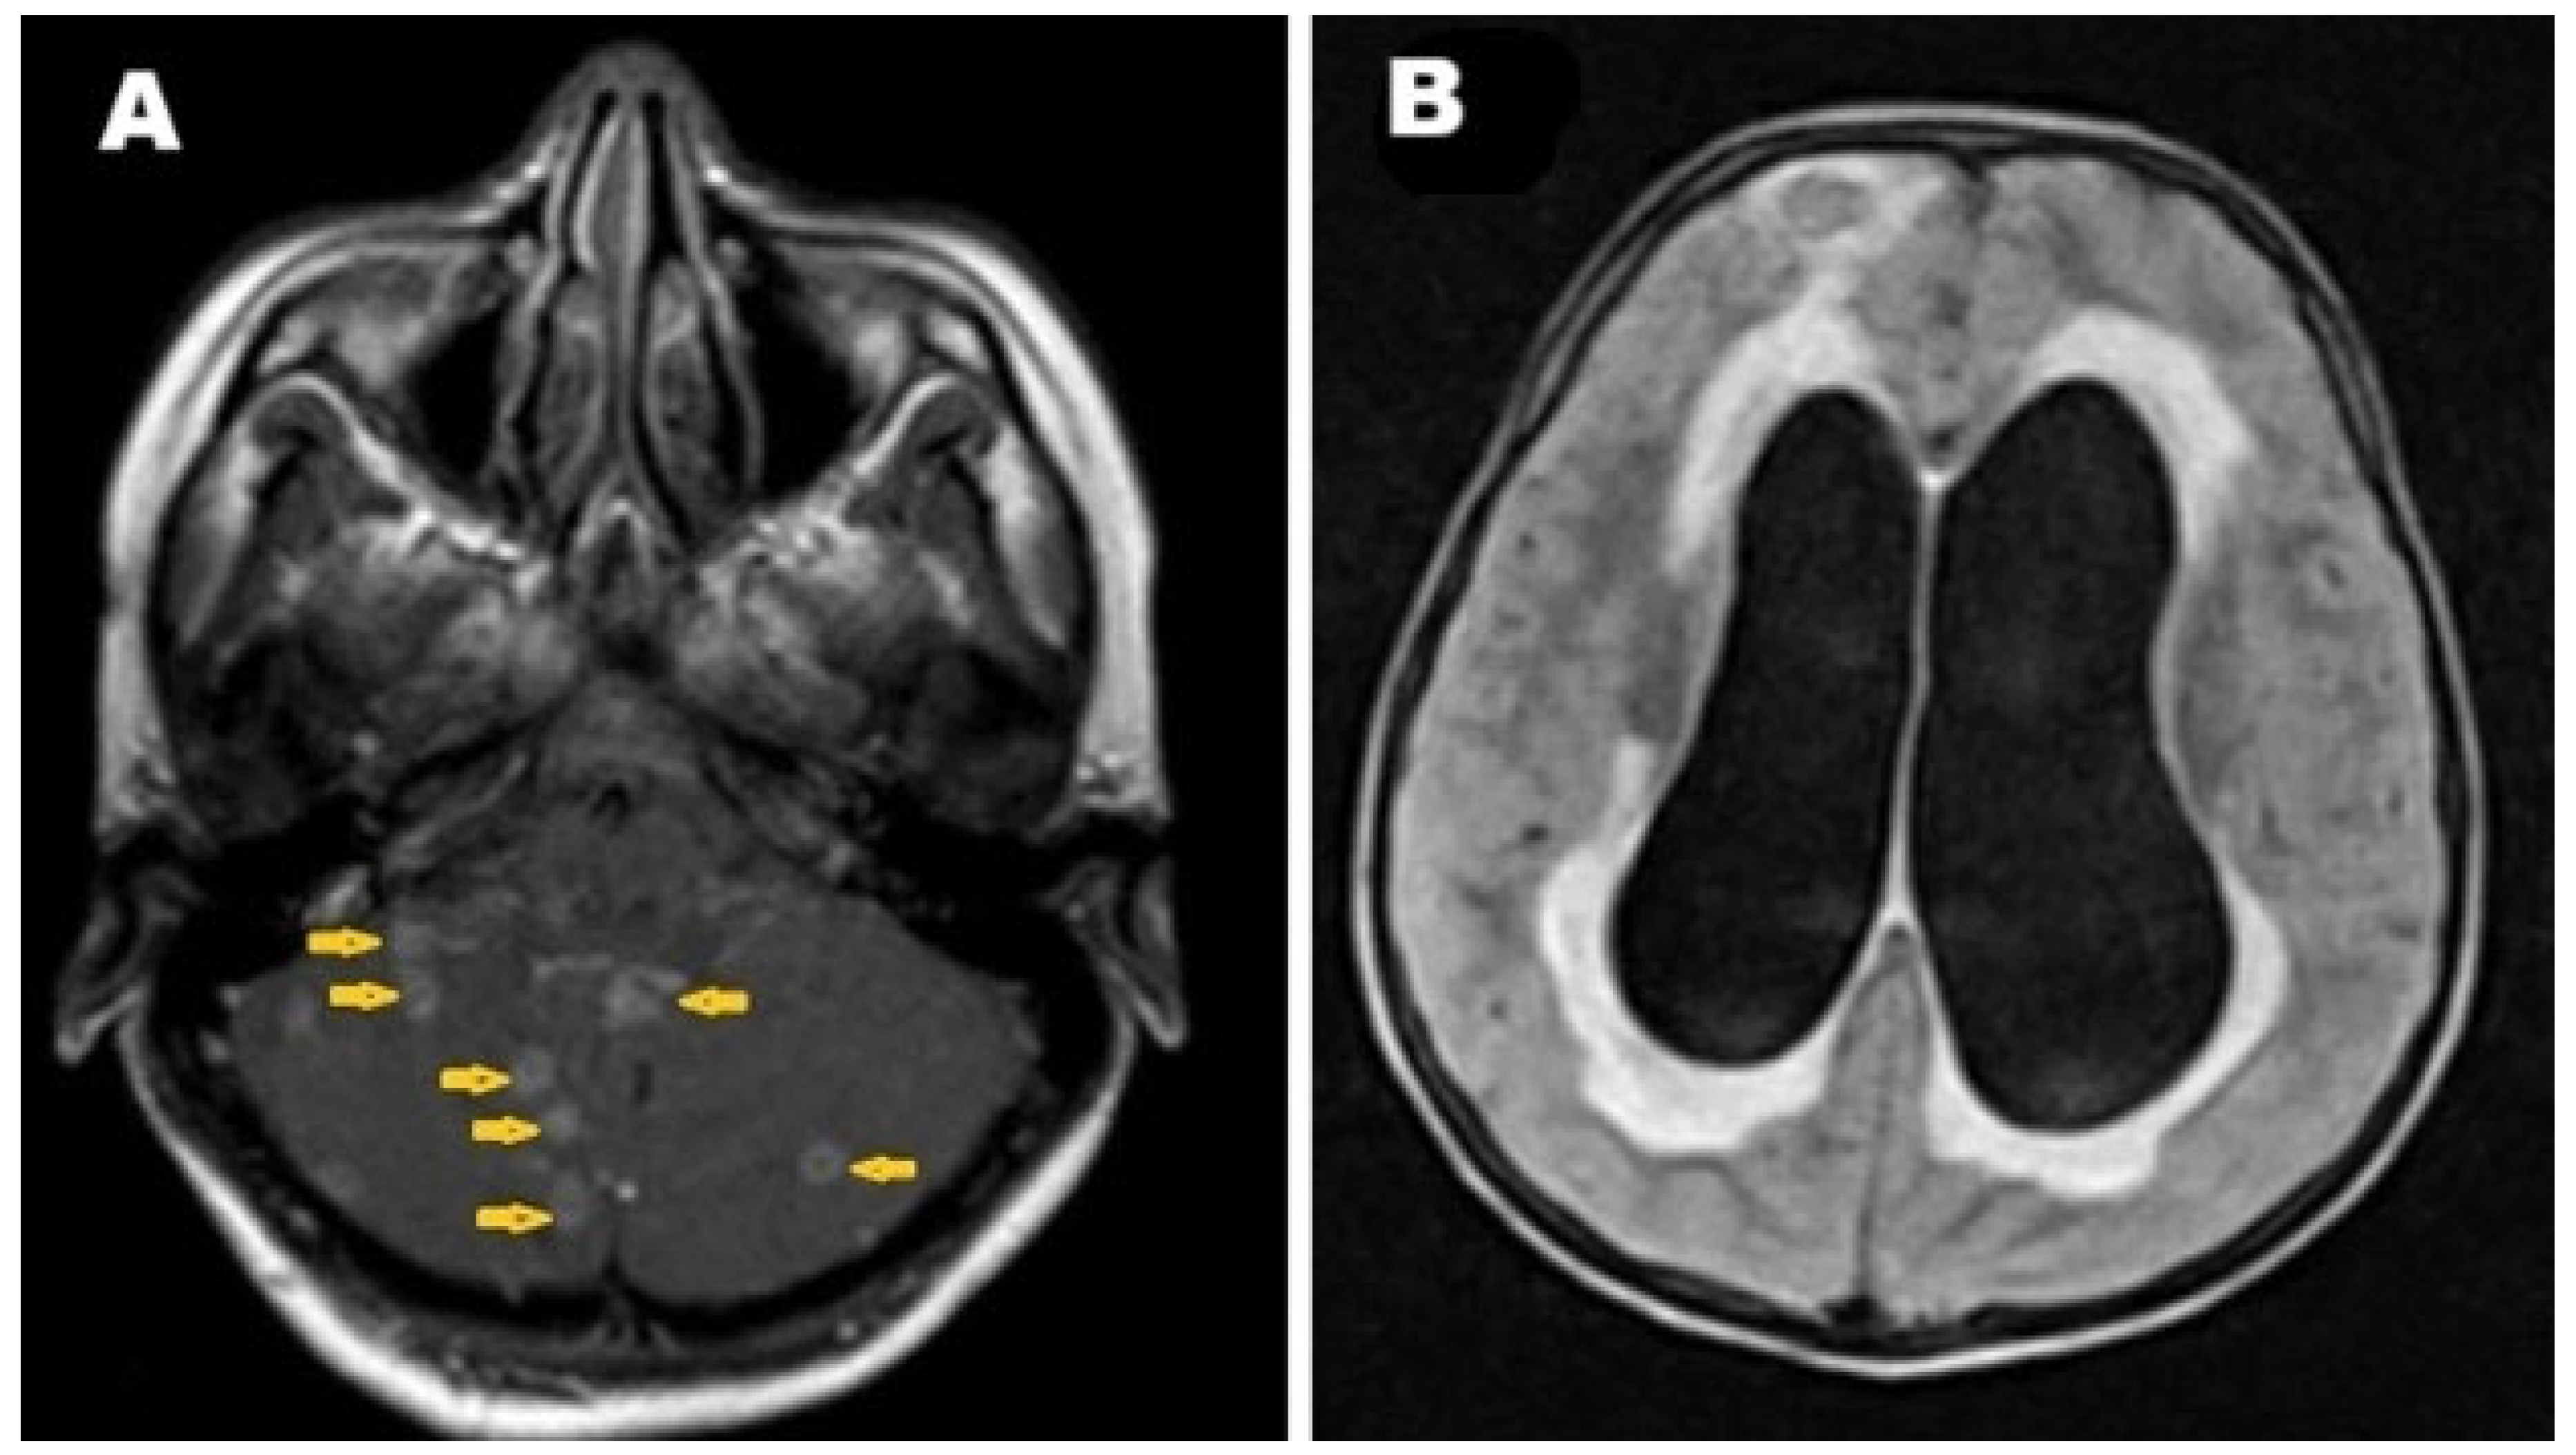

2. Case Presentation